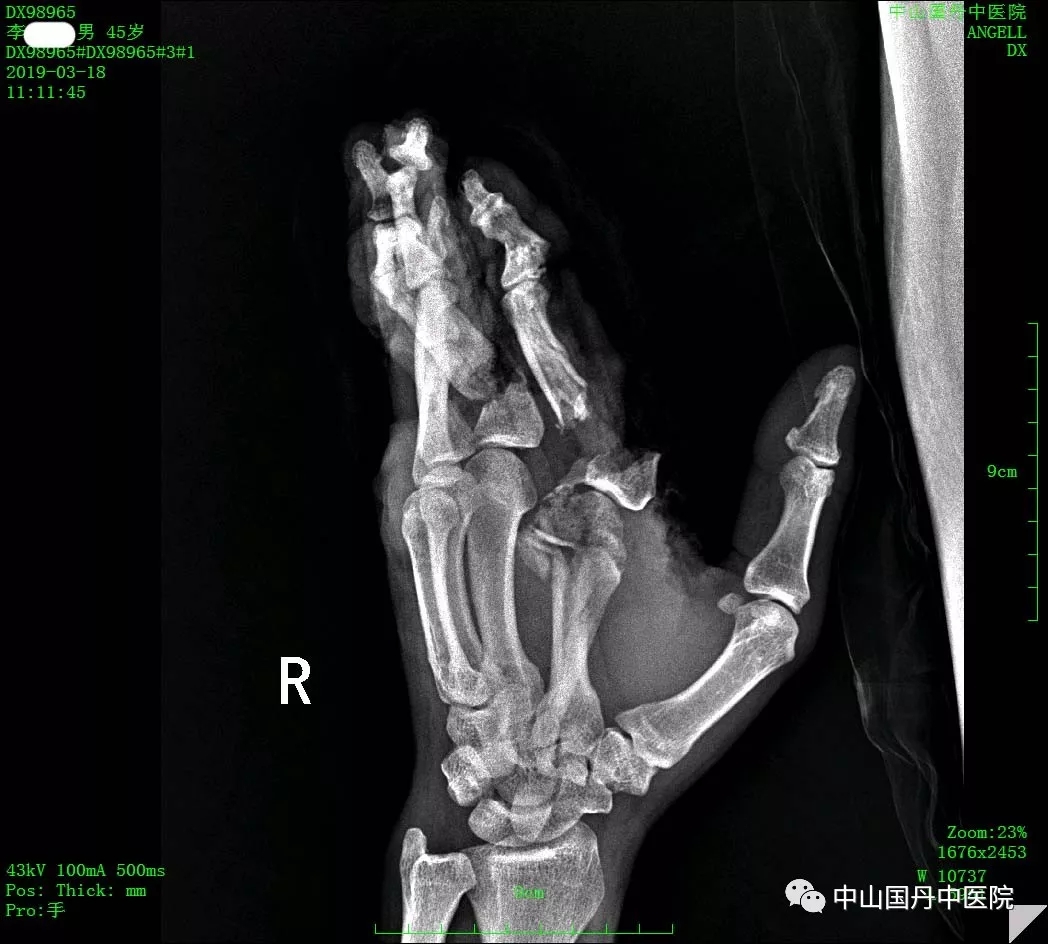

片子中,手掌骨头已损毁、脱套、不完全离断

外科主任胡彪表示:“这种手指已经被机器压得很烂(毁损、脱套以及不规则离断)的情况下,抢抓时间,恢复手指的血运功能是重点!”